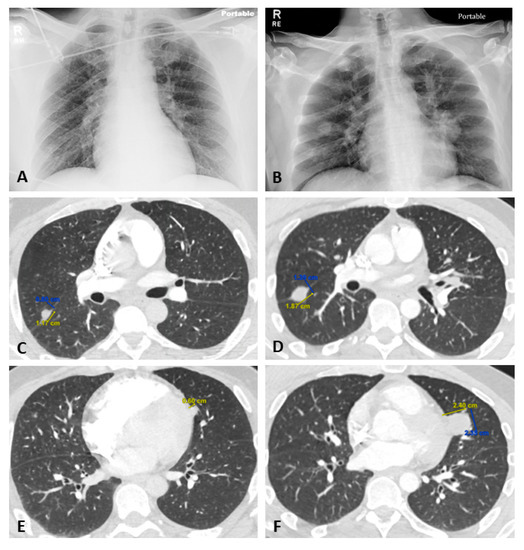

2.1. Case Presentation